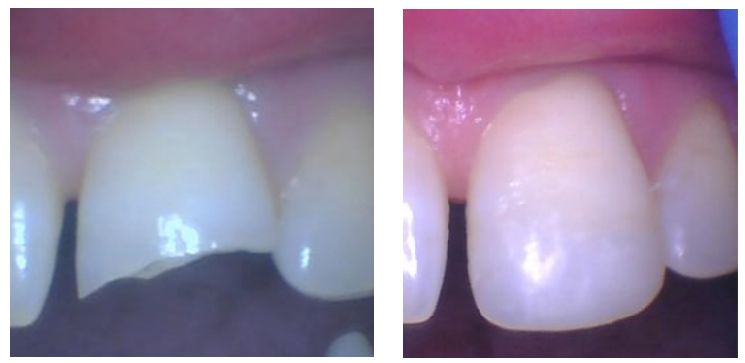

Real Success. Real Change